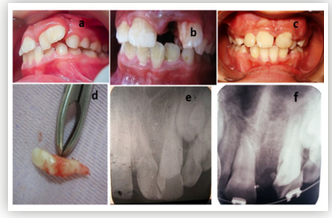

Case Report

Anesthesia for Fetus in Fetu with Difficult Airway, Skeletal Dysplasia and Hyperparathyroidism

Thuraya Abdullah, Yussra Solan, Muhammad J Ansari, Basmah Kaabi, Turki Al-Malki, Moteb Al- Otaibi and Essam Rabie